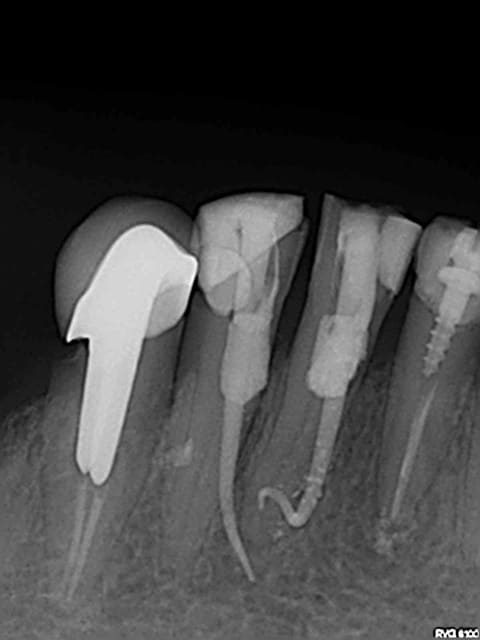

Oui bon, c'était la fin de la journée, la dame elle me disait qu'elle avait très mal, je lui ai fait les pulpecs vite fait avant d'aller regarder "les Anges", et cette conne elle revient le lendemain matin en me disant qu'elle a bien plus mal qu'avant ! Y'a vraiment des sans gêne, j'vous jure ! Je lui ai dit "c'est normal Madame, ça va passer" et lui ai confirmé son rendez-vous de la semaine prochaine pour l'empreinte des ICs ! Non mais !

Boire ou dévitaliser, il faut choisir !

Le cône est en place, mais bon ?

Je connaissais pas les implants immédiats en gutta. Tu préfères pas passer directement au grade 4 au moins ?

endos KO implants OK???

bizarre que çà saigne pas avant d'obturer...ni qu'un localisateur d'apex ne s'affole dans ce genre de situation...

Blague à part, cette dame est venue nous voir (c'est mon collègue qui l'a reçue) parce qu'elle avait encore mal après les pulpecs d'un autre praticien (un confrère installé pas très loin, proche de la retraite et qui, me semble-t-il, a depuis longtemps perdu le feu sacré de la dentisterie), elle est vraiment retournée le voir le lendemain, il lui a vraiment dit que c'était normal et, toujours d'après elle, elle avait vraiment rendez-vous la semaine suivante "pour les couronnes."

Ce n'est pas la première qui passe chez nous après une visite chez lui, mais là, je me devais de partager cette radio !

putain il a eu le "S" apical de la 41!

"putain il a eu le "S" apical de la 41!"

C'est ce que je me suis dit en regardant la radio en tout petit et sans mes lunettes : c'est quoi cette endo de ouf???

l'important c'est de finir à l'apex: objectif réussi pour 41